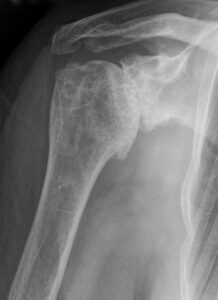

Розриви манжети, звичні вивихи, переломи ключиці й головки плеча лікуємо у три етапи: діагностика, малоінвазивна хірургія, персональна реабілітація.

Читати далі →